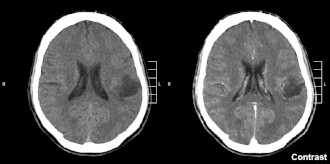

El glioma es un tipo de neoplasia que se produce en el cerebro o en la médula espinal. Se llama glioma, ya que surge a partir de células gliales. Su ubicación más frecuente es el cerebro.[1]

Los síntomas de los gliomas dependen de qué parte del sistema nervioso central se ve afectada. Un glioma cerebral puede causar dolores de cabeza, náuseas y vómitos, convulsiones y trastornos como consecuencia del aumento de la presión intracraneal. Un glioma del nervio óptico puede causar la pérdida visual. Un glioma en la médula espinal puede causar dolor, debilidad o entumecimiento en las extremidades. Los gliomas no metastatizan por el torrente sanguíneo, pero puede propagarse a través del líquido cefalorraquídeo incluso hasta la médula espinal.

Los gliomas de alto grado estimulan la formación de nuevos vasos que carecen de barrera hematoencefálica. Tienen extensas áreas de necrosis e hipoxia. Se diseminan a través de las vías nerviosas de interconexión del propio cerebro, sin tener límites definidos ni siquiera en el momento del diagnóstico. En el 80% de los casos recidivan en un margen de 2 cm de la zona de resección tumoral, incluso cuando la extirpación es macroscópicamente completa. Por lo general, los gliomas de alto grado volverán a salir, incluso después del tratamiento quirúrgico completo y del tratamiento con radioterapia y quimioterapia.